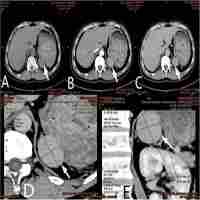

| Abstract | Background During embryogenesis, the spleen undergoes intricate developmental processes, originating from mesenchymal cells in the dorsal mesentery. An accessory spleen, a common anomaly found in autopsies and abdominal CT scans, can often be mistaken for different types of tumors. To the best of our knowledge, this is the first case in Syria documenting the occurrence of 3 accessory spleens in a patient who had previously undergone splenectomy. Case presentation A 33-year-old male presented with right hypochondrium pain, sharp and radiating to the right flank, exacerbated by movement and large meals. Past medical history included mild Irritable Bowel Syndrome (IBS) and splenectomy due to a traumatic accident in childhood. On admission, vital signs were stable, with abdominal tenderness in the right upper quadrant. Laboratory investigations showed normal values. Ultrasound revealed a lobulated mass at the right adrenal gland (4.5 × 5 cm) with an isoechoic to hypoechoic texture. Multi-slice computed tomography (MSCT) Scan showed multiple nodules in the right adrenal gland, regular in shape, exerting a compressive mass effect, and significant lymphadenopathy around the abdominal aorta. Elevated metanephrine levels raised suspicion of an extra-adrenal pheochromocytoma. Laparoscopic surgery was performed, revealing accessory spleens and normal adrenal tissue with no malignancy. Conclusion Healthcare providers should consider accessory spleens as a differential diagnosis for masses near the adrenal glands. Multiple accessory spleens in the adrenal region can complicate cases. Accessory spleens in uncommon locations like the adrenal glands can be challenging to diagnose and manage. |